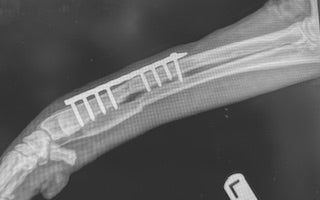

Fracture Repairs

Broken bones require timely, specialized care. We perform internal and external fracture repairs using advanced techniques such as pins, plates, or external fixators, depending on the location and severity of the fracture.